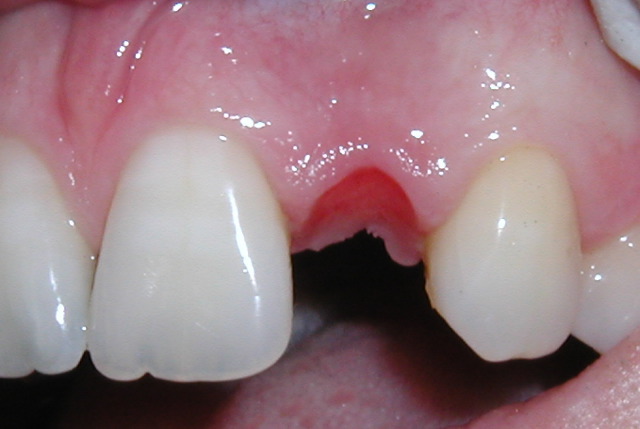

| Missing tooth | Implant placed |

This procedure allows the placement of an implant with a temporary crown on the same day with no need for sutures. There is so little discomfort that most patients go back to work and use only mild "over the counte" type medications.